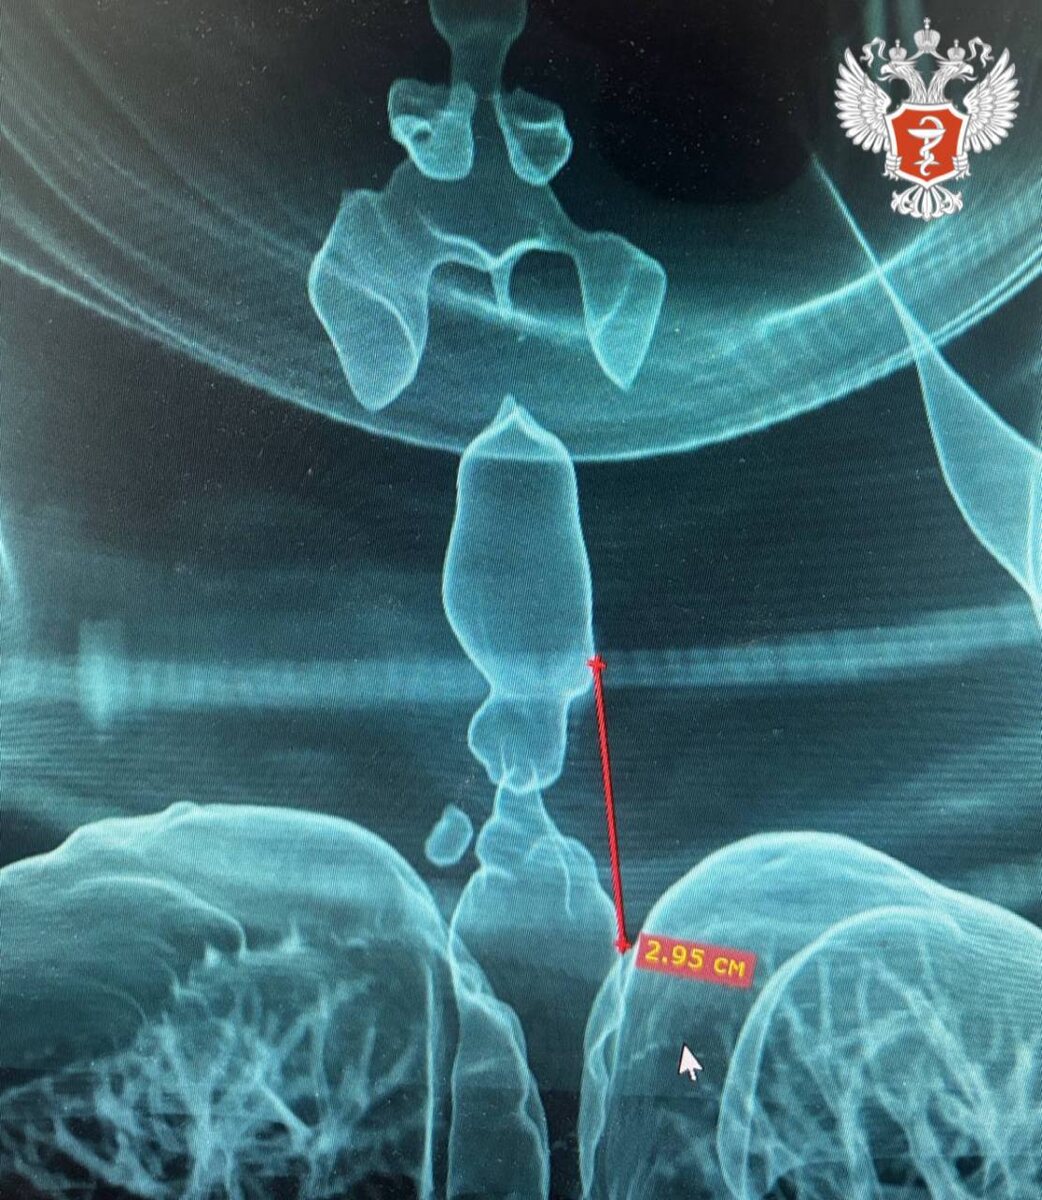

Обследование выявило рубцовое сужение трахеи протяжённостью 2,95 см при минимальном просвете всего 5 мм, угрожавшее жизни. Для точной оценки поражённого участка специалисты создали 3D-модель дыхательных путей пациентки.

В Центр торакальной хирургии Городской клинической больницы №9 г. Ижевска поступила женщина с тяжёлым нарушением дыхания после ДТП. Пациентка долгое время находилась на аппарате искусственной вентиляции лёгких, после чего у неё развилась выраженная одышка и шумное дыхание.

В ходе операции врачи удалили поражённый участок и восстановили целостность дыхательных путей. До этого подобные операции проводились лишь в федеральных медицинских центрах.